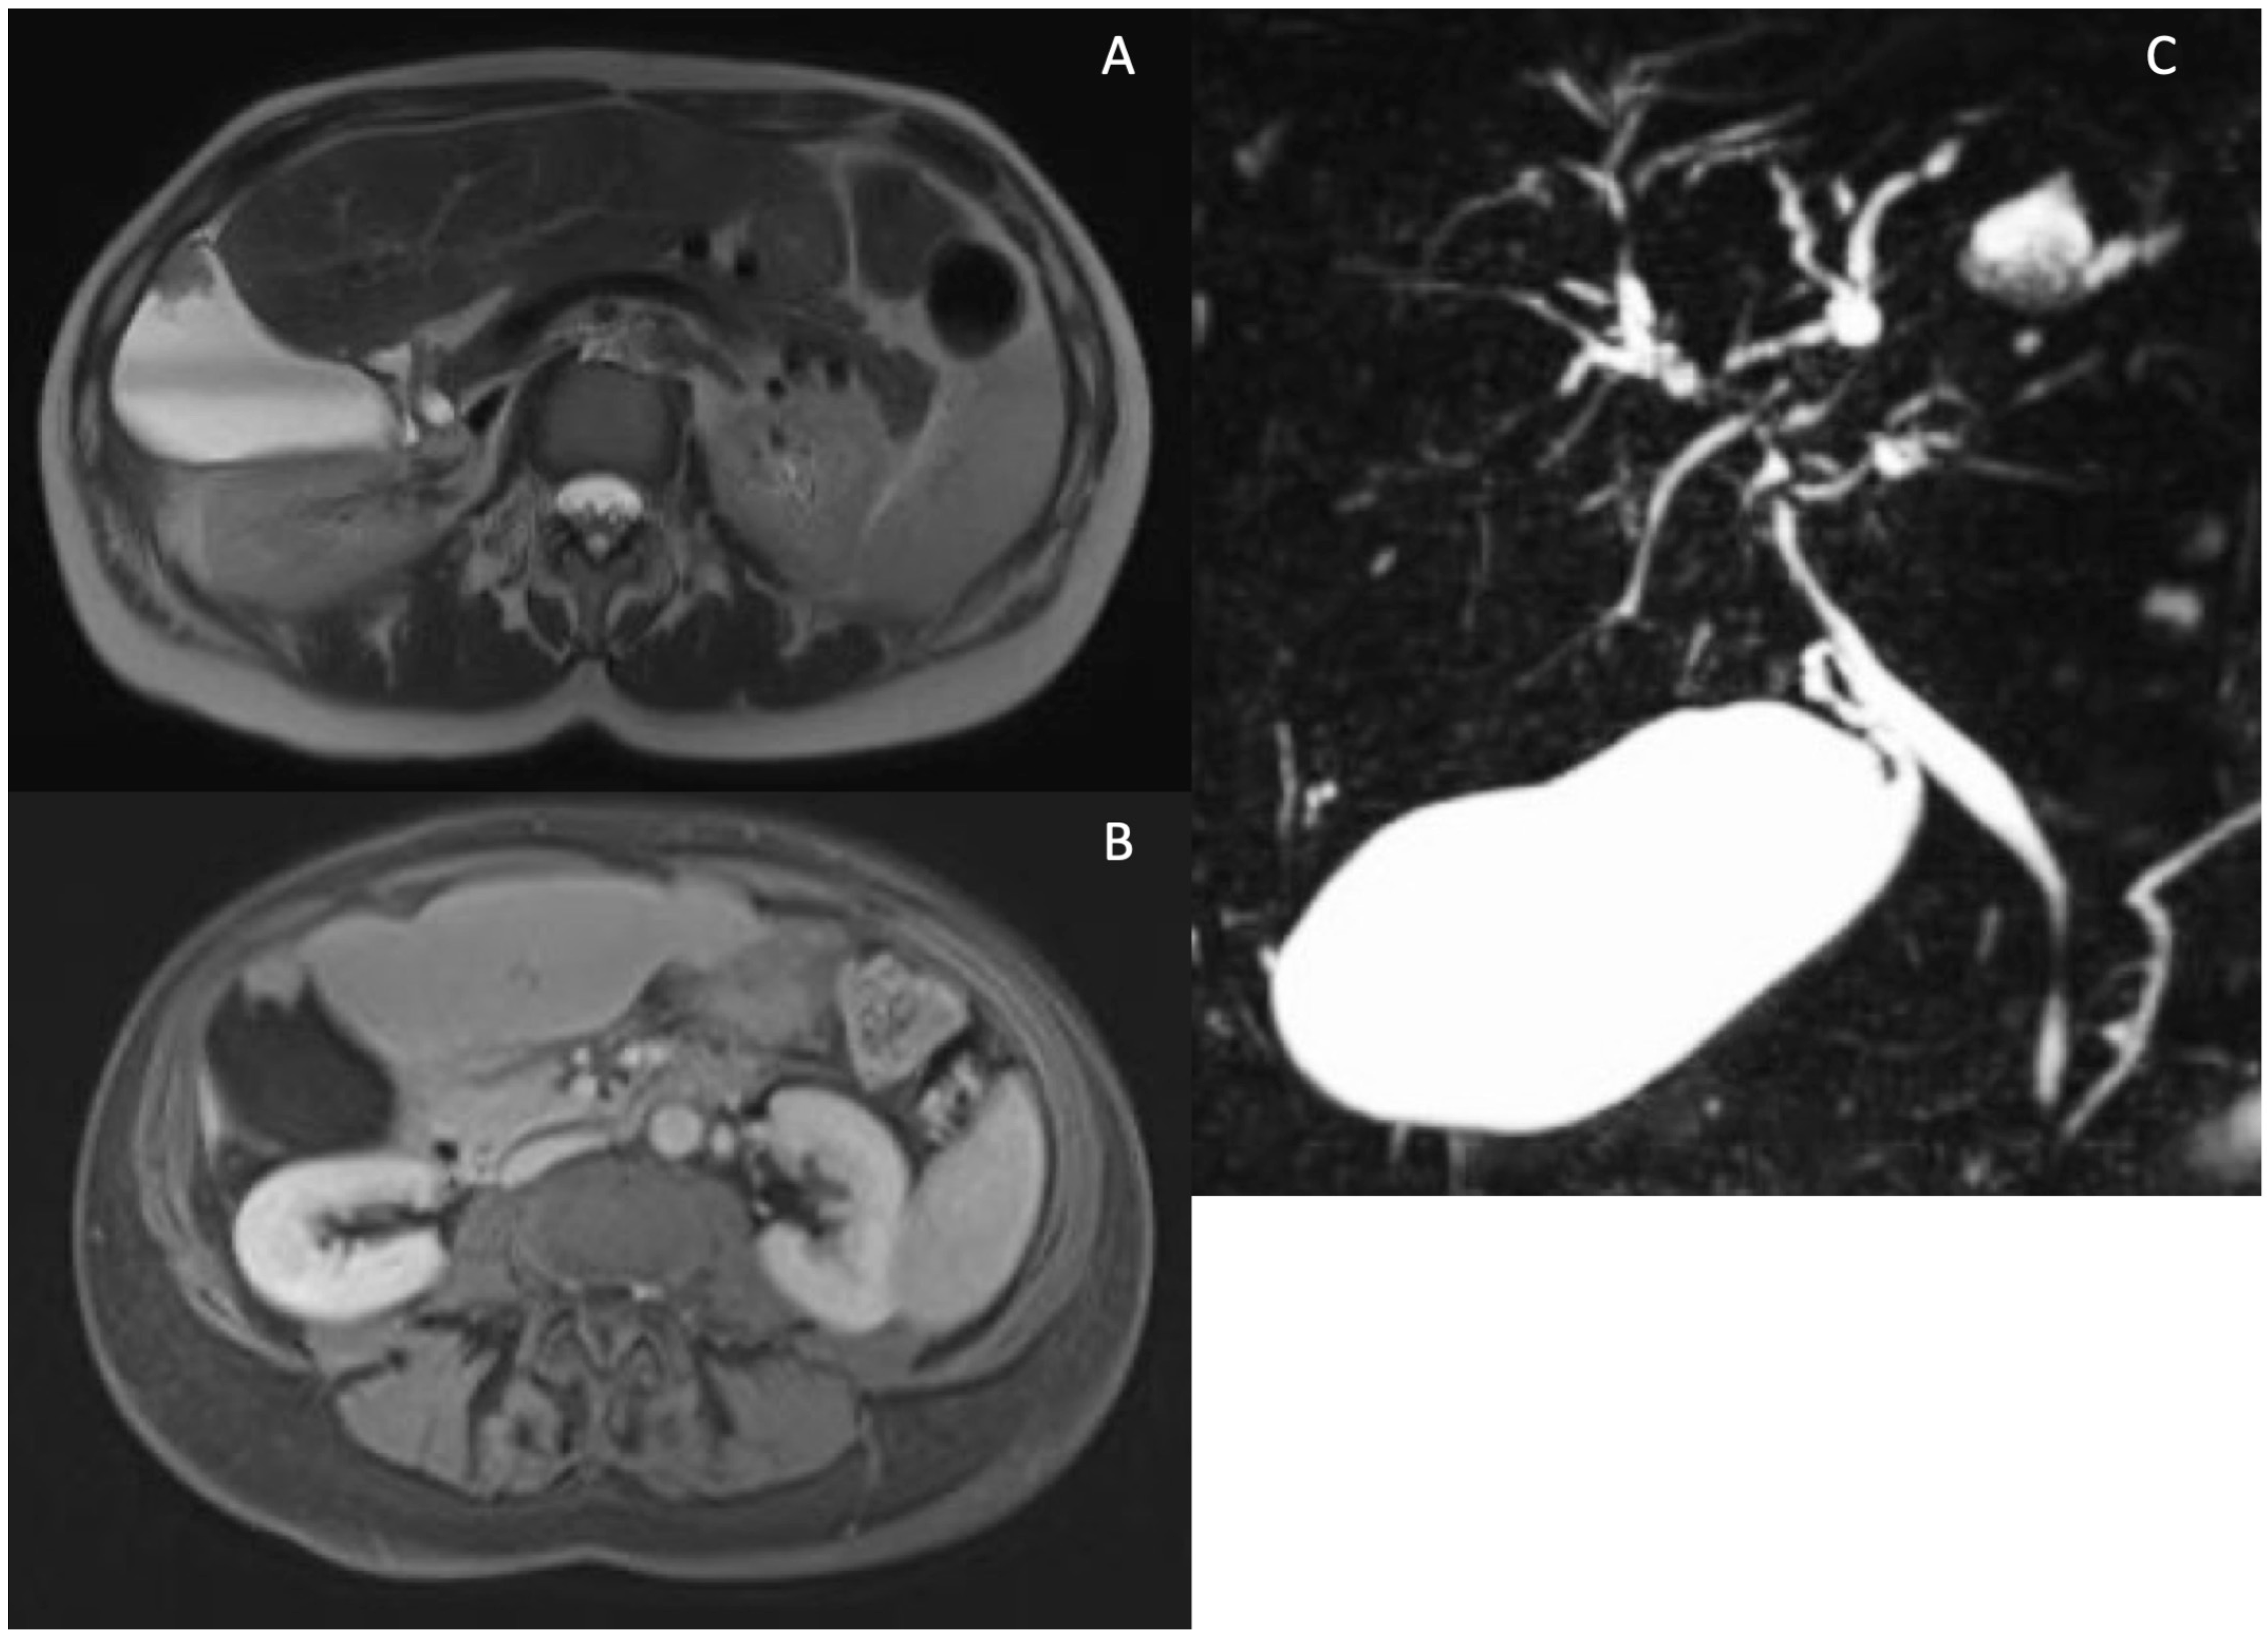

5. Technical Aspects of MRI in PSC

6. Cholangiographic and Liver Parenchymal Changes in PSC